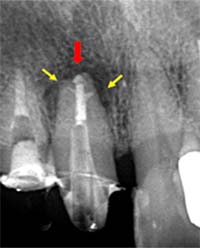

根尖封鎖の比較

![]() |

| MTA根充前 | MTA根充後 |

側枝の取り残し

| 術前 | 当院にて根充 |